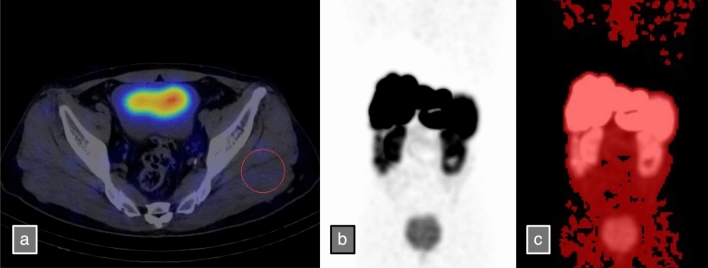

This study analyzed 111 PRRT cycles administered to 36 patients between September 2021 and August 2024. Late EDR-1 m was set as the dependent variable, whereas total radiopharmaceutical uptake (LUTtotal), dose per body weight, creatinine clearance (CCr), and albumin–bilirubin (ALBI) score were set as the independent variables in the multiple regression analysis. LUTtotal was calculated using SPECT/CT data acquired after the patient left the radiation therapy room, defining the volume of interest (VOI) as the area with SUVmean + 2SD or higher in the skeletal muscle. The VOI volume multiplied by the SUVmean was used to define LUTtotal. In addition, using [111In] pentetreotide SPECT/CT data, the total radiopharmaceutical uptake (OCTtotal) was calculated in a manner similar to LUTtotal, and its correlation with LUTtotal was examined. A predictive equation for Late EDR-1 m was developed using the results of the multivariate analysis, and its performance was tested using subsequent cases between August 2024 and January 2025.